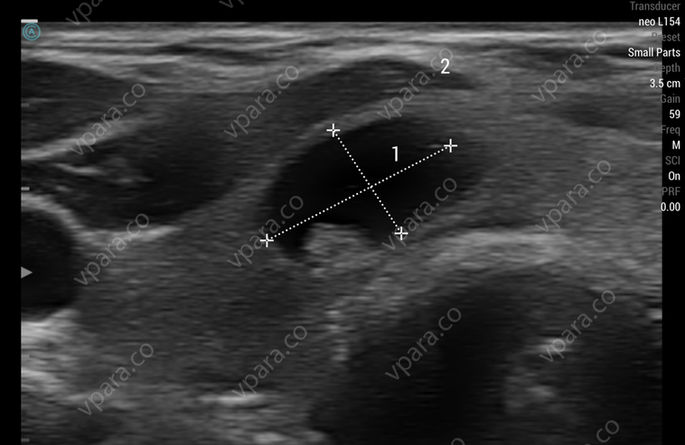

Thyroid Cyst

Apache neo L154 scanned with iPad Air (4th generation). Portrait mode.